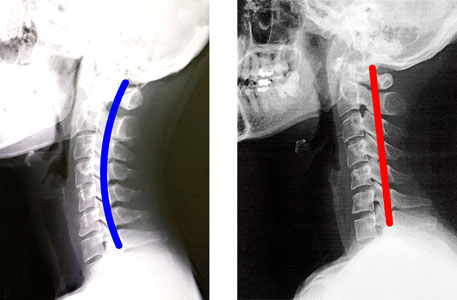

ストレートネックとはその名の通り、首の骨「頚椎」がまっすぐな状態になってしまっていることを言います。

本来であれば、頚椎は緩やかなアーチ状になっており、それによって頭の重さを支えたり、背骨全体の湾曲を作ることで適切な姿勢を保っています。